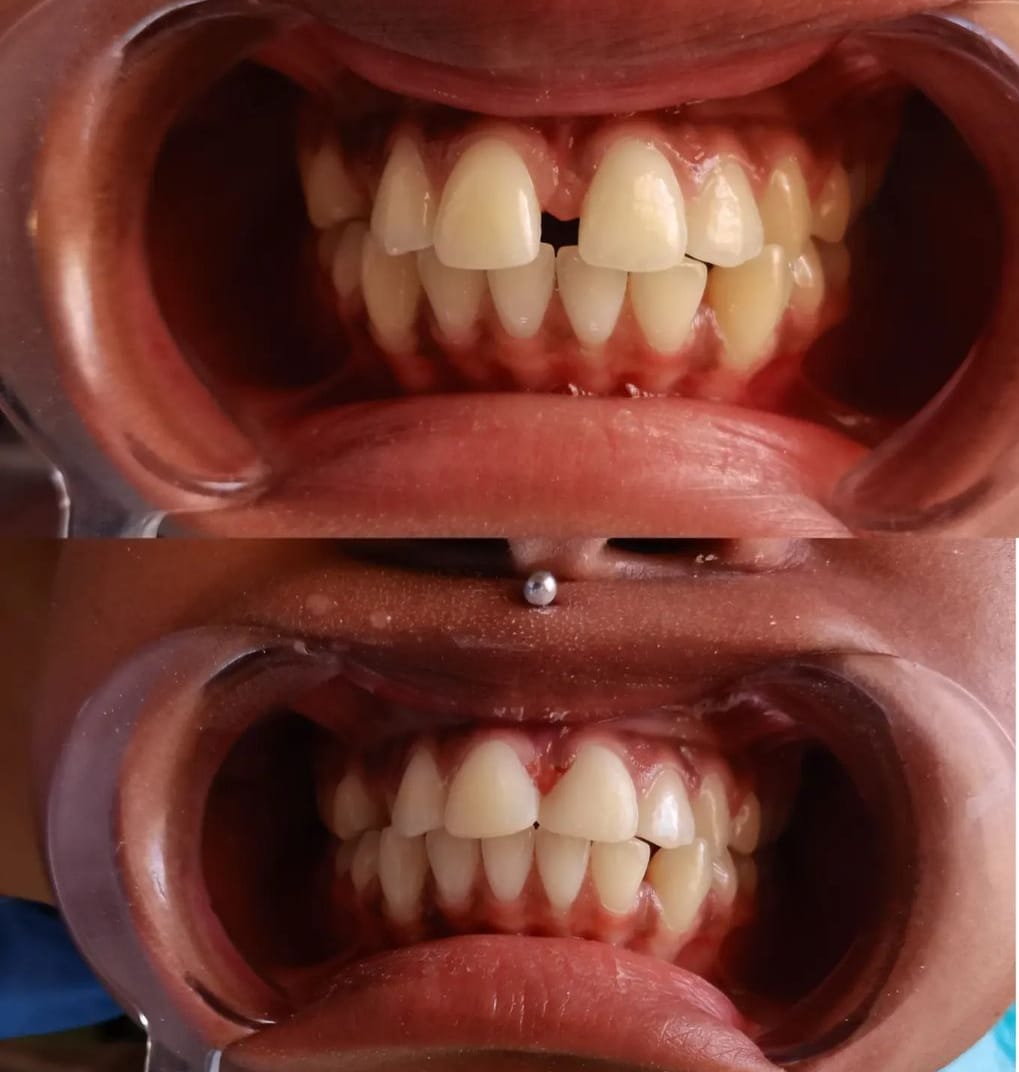

Our Latest Work